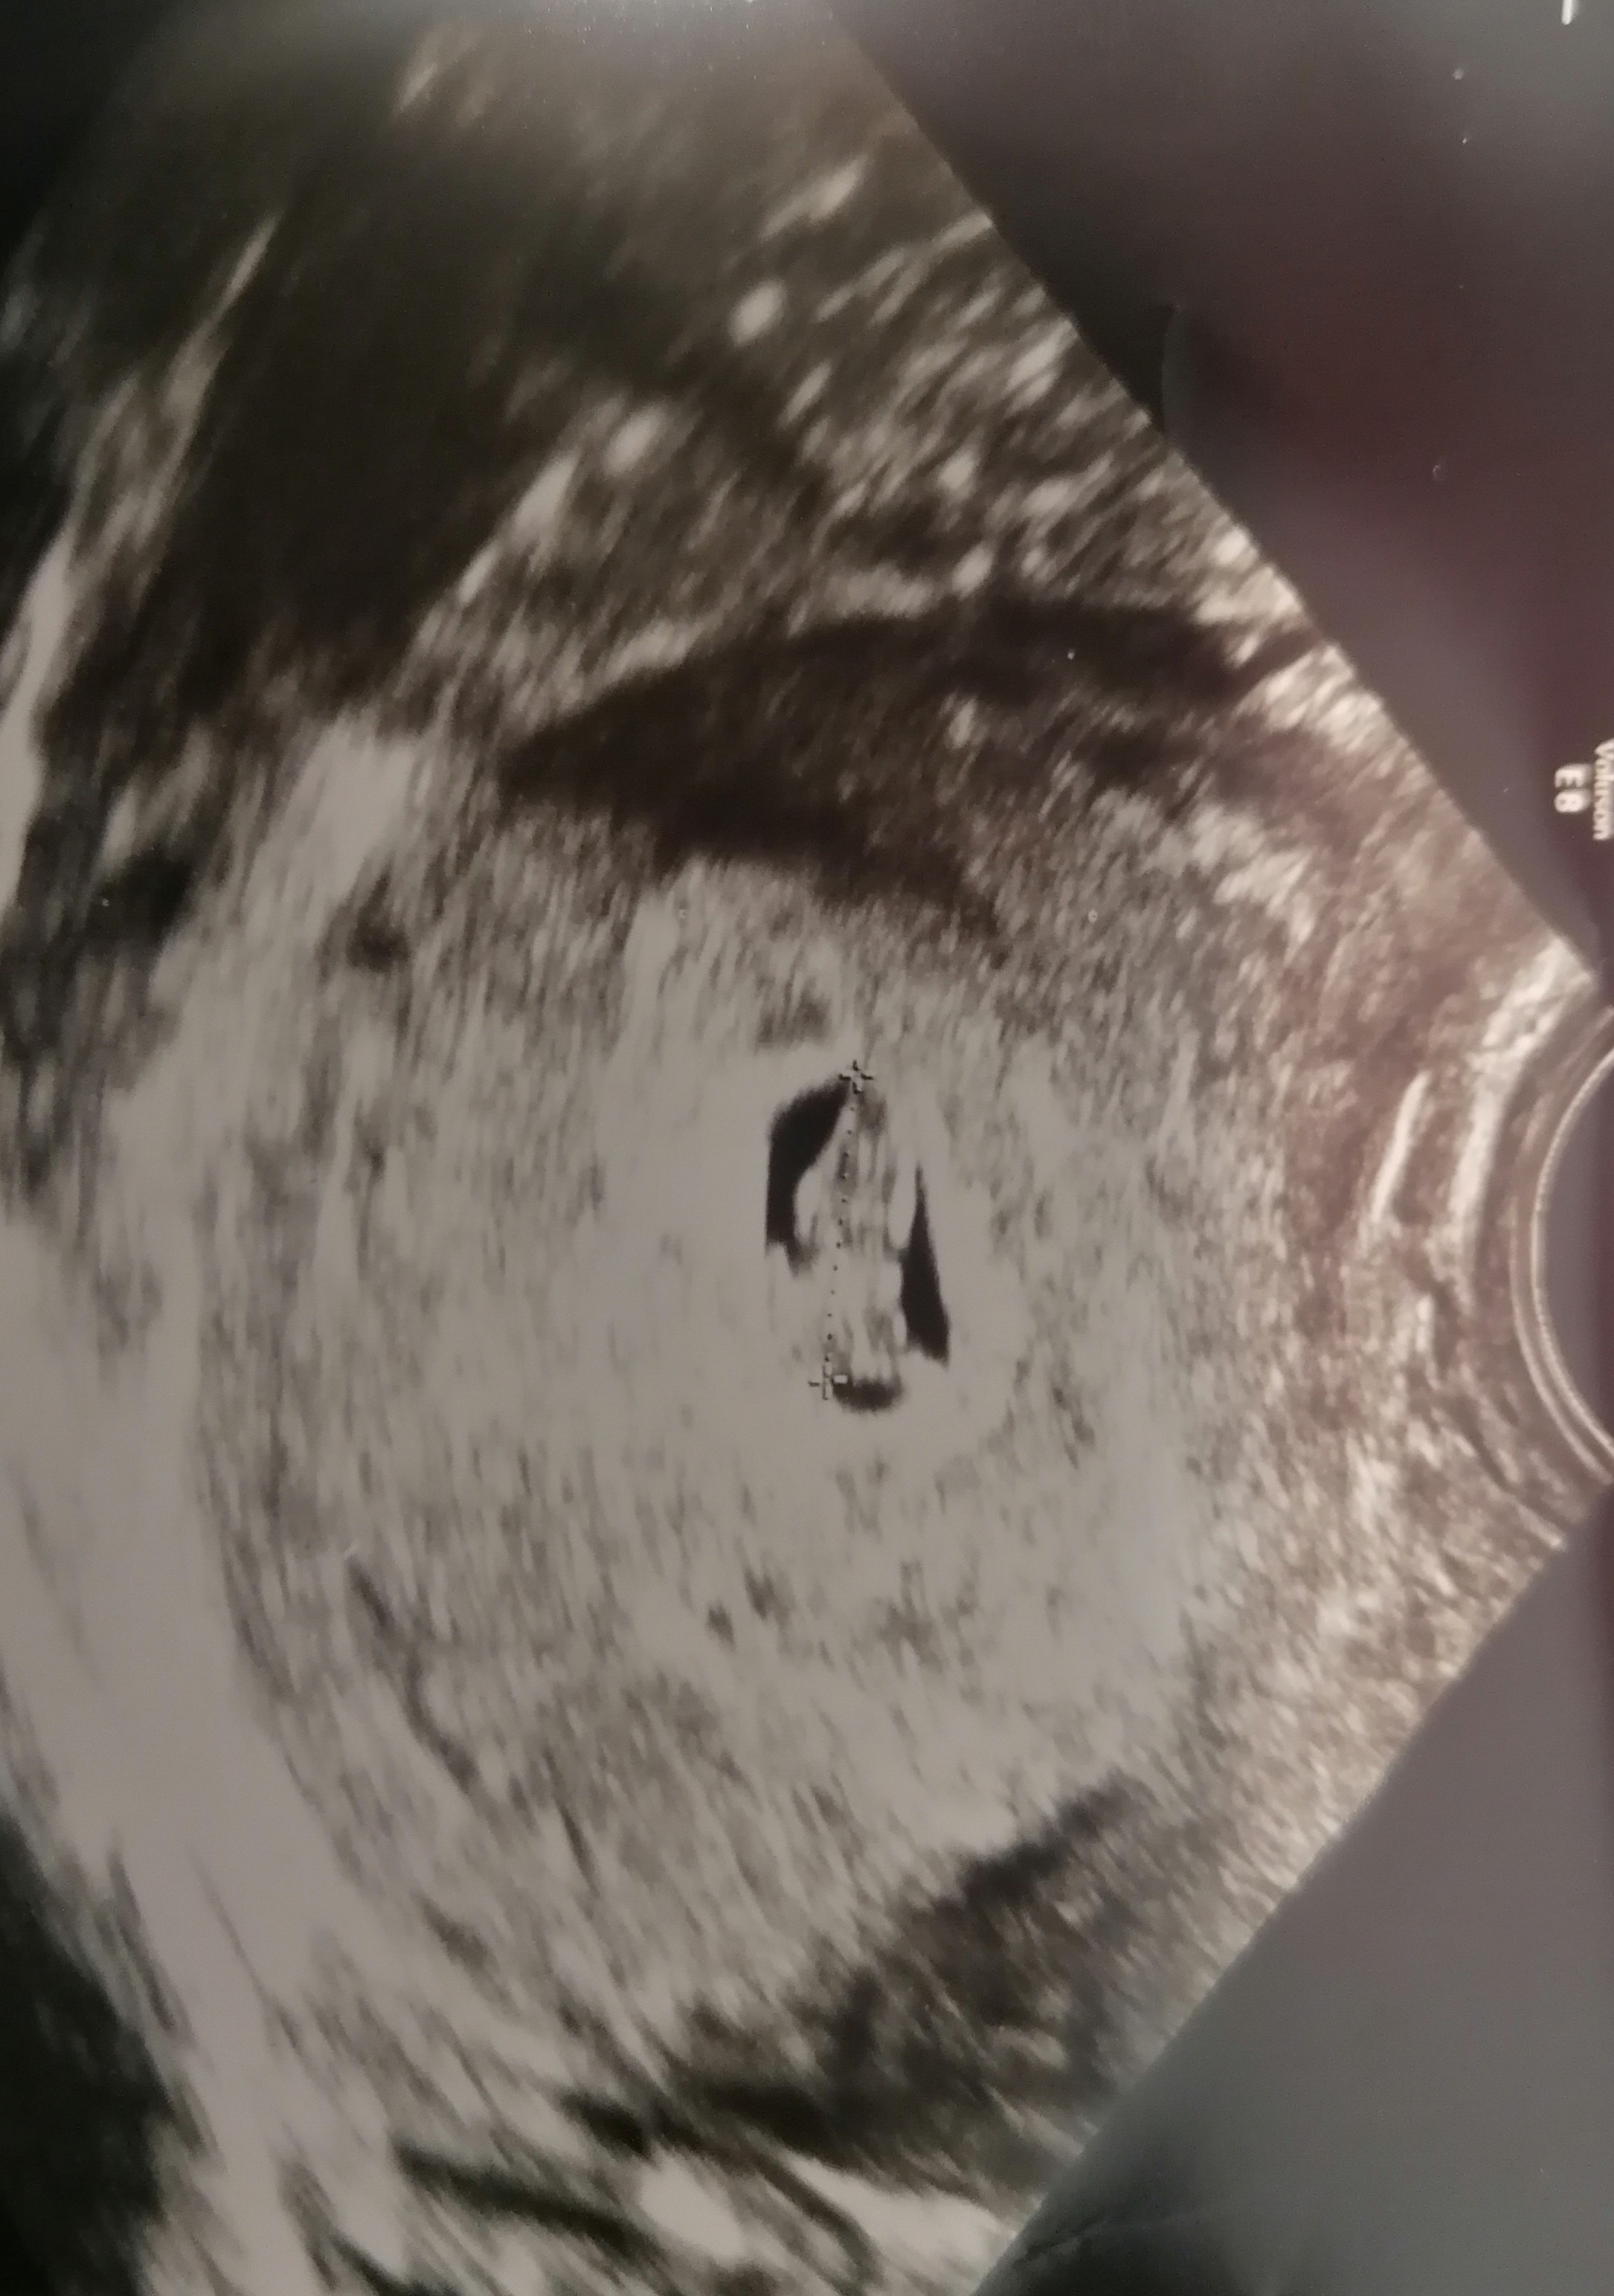

Mały pęcherzyk w porównaniu do zarodka.

U mnie wygląda to tak, więc widac gołym okiem na usg że pęcherzyk jest malutki